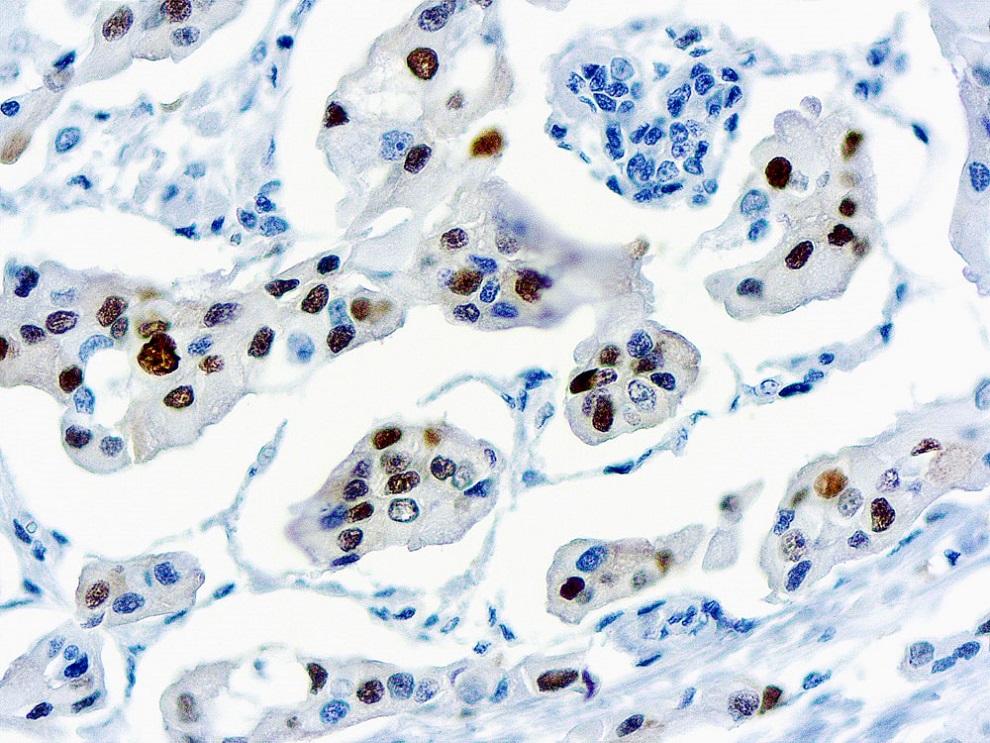

Actin Alpha Smooth Muscle

This antibody is specific to a-smooth muscle isoform of actin. It reacts with smooth muscle cells of vessels and different parenchymes. This antibody does not cross-react with ß and ?-cytoplasmic, a-sarcomeric and a-myocardial actin isoforms.ng paraneoplastic syndromes by secreting ACTH.

Clone 1A4

Application IHC